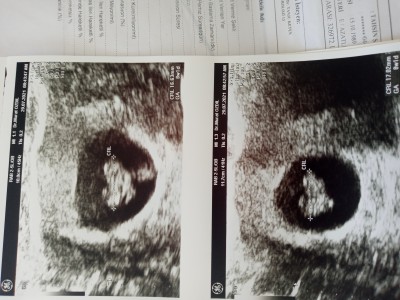

:angel: mrb hanımlar sadece tahmin edebilir benzetme yapabilirsiniz

ama lütfen kırıcı olmayın 11 yıldır bebek istiyorum ve ilk önce sağlıklı olması tabi  merak ediyorum

Cinsiyet tahmini benzetmesi .......?

Usg de yeni fark ettim bebeğim kalp gibi duruyor....  <3